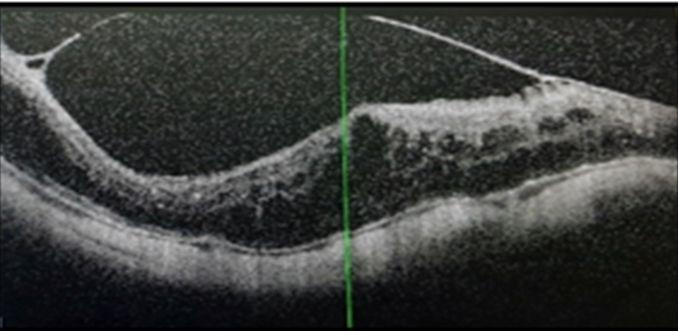

טומוגרפיה קוהרנטית אופטית, או בדיקת OCT סטנדרטית, היא בדיקת הדמיה הכרחית של פנים-העין, המשמשת לאבחון מחלות עיניים ברמת דיוק מיקרוסקופית. בדיקה זו משמשת לאבחון ולמעקב של מחלות הפוגעות במרכז הרשתית (המקולה), בהן ניוון מקולרי תלוי-גיל (AMD), מחלת הסוכרת, חסימה ורידית, ועוד. בנוסף, בדיקת ה-OCT חיונית מאד באבחון גלאוקומה, וגם במעקב אחר המחלה תוך כדי הטיפול. הבדיקה חשובה מאד לתמיכה באבחון גלאוקומה גם במצבים פחות שכיחים, כגון כשהלחץ התוך-עיני תקין (Normotension glaucoma).מאידך היא יכולה לשלול חשד גלאוקומה גם כשהלחץ מעט גבוה, ולחסוך טיפולים מיותרים במשך שנים. בדיקת ה-OCT איננה פולשנית, קצרה, בטוחה-מאד, ללא מגע וללא כל כאב. מכשירי OCT נמצאים בכל מחלקות העיניים של בתי החולים ובמרפאות עיניים שונות.

הבדיקה אינה מספקת מידע על זרימת הדם בנימים (כלי-הדם הקטנים ביותר) במחלות הנ"ל. אבחנה של פגיעה בזרימה ובאספקת הדם חשובה במיוחד כיון שהיא קריטית בהתהוות המחלה ומשפיעה על התקדמותה. פגיעה באספקת הדם יכולה אף לגרום לסיבוכים של המחלה עצמה, כגון עקב היווצרות כלי-דם חלשים אשר עלולים לדמם לתוך העין ולגרום להחמרה במחלה אם לא יטופלו במועד. אולם, ה-OCT הסטנדרטי בד"כ לא מאבחן פתולוגיות אלו.

מדובר בבדיקה חדשנית אשר נמצאת בשימוש קליני בשנים האחרונות. הבדיקה מבוססת על תכנה מתקדמת אשר מבצעת 100,000 צילומים בשנייה אחת וכך מאפשרת לבחון בדיוק רב את זרימת הדם בנימים הפנימיים בעין [תמונות 5,6]. זוהי למעשה הבדיקה היחידה בגוף שמראה את בריאות הנימים הפנימיים בבדיקה שאינה פולשנית. תוצאות הבדיקה מספקות מידע חיוני על זרימת דם תקינה או חסרה, לרבות על היווצרות נימים חלשים שיכולים לדמם; על תגובת הנימים החולים לטיפולים; ועוד. הממצאים יכוונו להחלטות הטיפוליות. בדיקה זו כבר נעשית כיום במספר מחלקות עיניים בארץ ובמרפאות עיניים שונות.